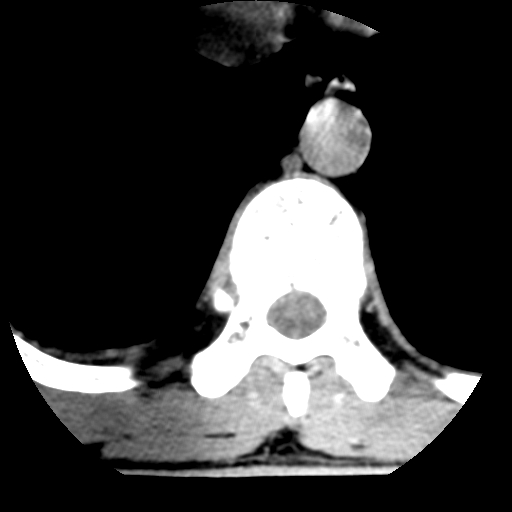

男,31岁,从6米高处坠落伤两天,腰背部疼痛,临床要求ct扫描胸10-腰1。请大家帮忙看看骨质有问题吗?

t12、l1锥体前缘轻度楔形变,平扫示椎体前缘骨小梁欠规整,第9幅图示椎体前缘骨质不连续,结合外伤史考虑椎体轻度压缩骨折。

楼主扫描层厚可能较大,每个椎体只有三个层面.

从所示层面分析,无明确骨折征象,象类似病人我个人会建议mri除外骨挫伤.

从上查骨窗第九片椎体前缘皮质显示断裂.压缩骨折?